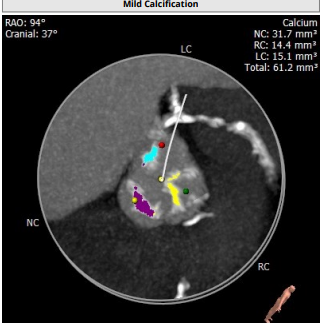

超声报告:

左冠高度:10.6mm,右冠高度:14.5mm。

钙化积分:61.2mm³,轻度钙化。